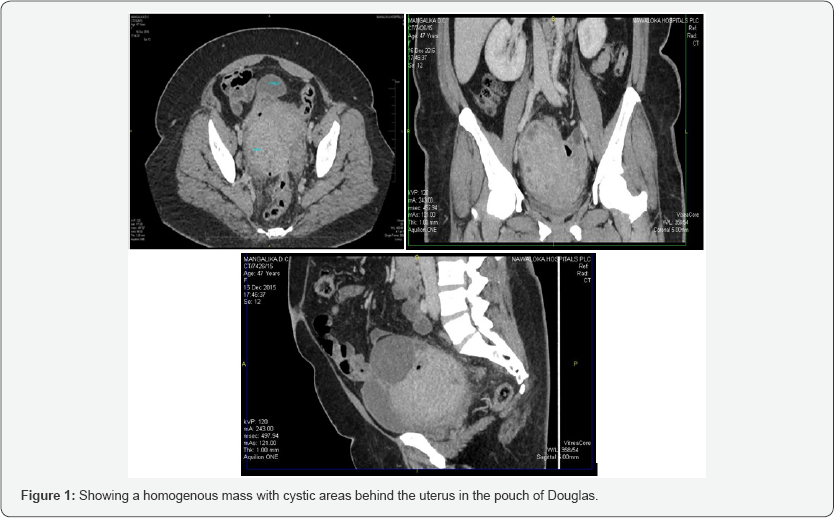

Her body mass index was 32. Weight was 89kgs. She had pallor and bilateral ankle oedema. There was no generalized lymphadenopathy. Abdominal examination revealed attended vague pelvic mass with irregular margins. There was no free fluid. Vaginal examination revealed a tender pelvic mass of 18 week size, with restricted mobility. Vaginal examination was extremely painful. Hence it was decided to proceed with an ultra sound examination which revealed a homogenous pelvic mass and an ill-defined uterus. Subsequent CT scan showed a clear homogenous mass with cystic areas posterior to the uterus in the pouch of Douglas.